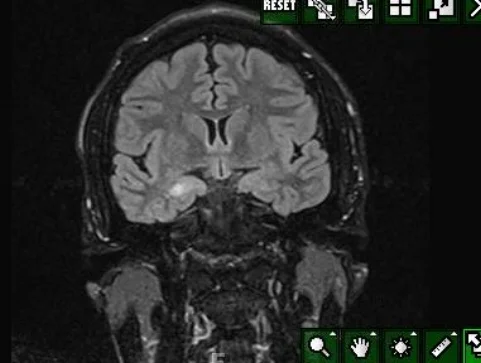

Our patient had neurocutaneous melanosis.  This is a rare disease characterized by pigmented nevi that affect not only the skin but the leptomeninges.  It was first described in 1861 by Rokitanski.  About 1/3 of the patients diagnosed are symptomatic often presenting with seizures, cranial nerve palsies, hydrocephalus or spinal cord involvement.  It is associated with Dandy-Walker malformation  in 10% of the cases. Our patient had presented with seizures as a child and on imaging was found to have melanosis in the R temporal lobe.  Because of intractable seizures he underwent a R temporal lobectomy in 2015.

melanosis in the R temporal lobe in our patient prior to surgery

The diagnosis is made on MRI with the melanocytes being hyperintense on T1 images. The deposits of melanocytes are most often seen in the amygdala, cerebellum and upper cervical cord. The pathogenesis is believed to be dysplasia of the neuroectodermal melanocyte precursor cells leading to proliferation of melanin in the skin and leptomeninges.  Patients with neurocutaneous  melanosis are at risk for malignant transformation to melanoma.  Malignant transformation occurs in 40-60% of symptomatic cases.